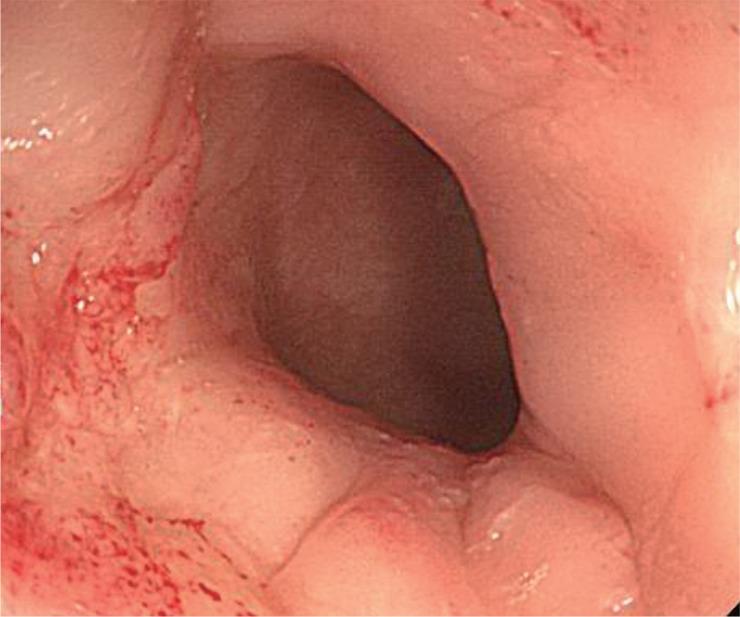

Successful management of colonic perforation with a covered metal stent.

Self-expandable stents are widely available for the treatment of perforation of the gastrointestinal tract. Because of the risk of migration, there has been no report of the use of self-expandable stents for the treatment of perforation of the colon or rectum. This is a report of successful treatment of iatrogenic colonic perforation during balloon dilatation of anastomotic stricture with a fully covered stent. Fully covered, self-expandable metallic stents can be considered useful tools for management of this condition.